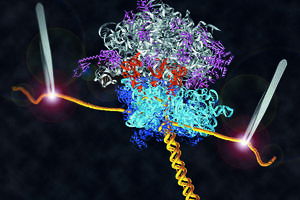

Capa

Uma proteína fundamental

Equipe explica o funcionamento da forma saudável do príon

Por Ricardo Zorzetto